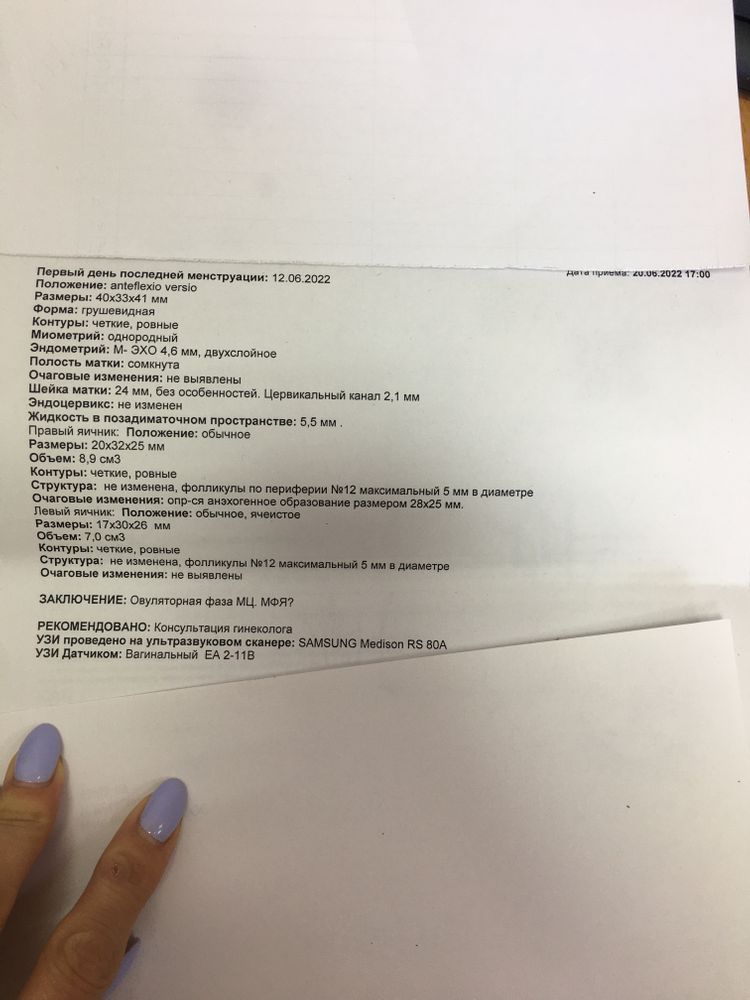

В итоге сходила вчера на УЗИ и толком ничего не поняла, врач не пояснила. Сказала что не может понять, как будто должна скоро начаться овуляция но при этом эндометрий маленький. Также поставила под вопросом МФЯ. Сказал сделать ещё раза фолликулометрию и иди к гинекологу с результатами.

Девочки посмотрите пожалуйста мои анализы и результаты УЗИ. Может вы что-то поймёте и мне объясните. Не могу ни как себя успокоить, переживаю. Даже работать не получается(